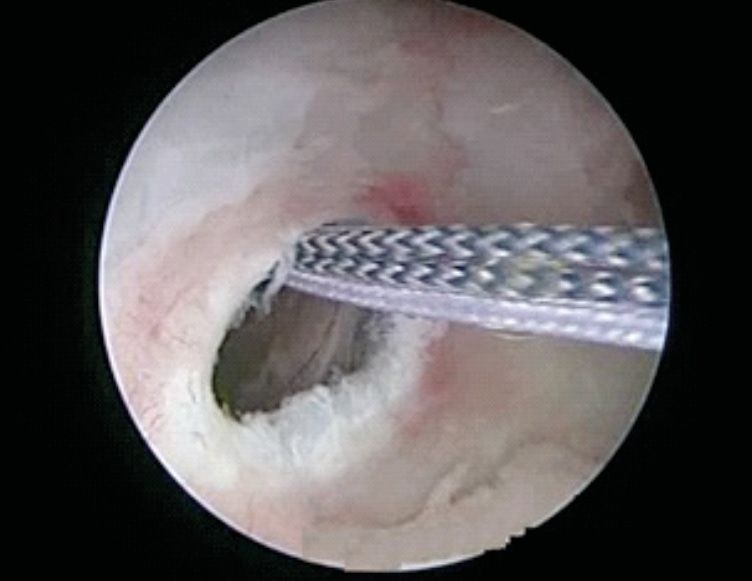

While viewing from an antero-superolateral portal, the radius of the inferior glenoid is measured by measuring the distance from the bare spot of the glenoid to the posterior glenoid rim (Figure 8). Then, one doubles the radius to obtain the inferior glenoid diameter (D). Then the distance from the anterior glenoid rim to the bare spot of the glenoid is measured. If there is no glenoid bone loss, this measurement should be the same as the posterior glenoid radius. If there is a glenoid bone loss (d), then the glenoid track measurement will be 0.83D-d. Now, the Hill Sach's interval (HSI) is measured. The HSI is the distance from the rotator cuff attachments to the medial rim of the Hill-Sachs lesion, and it is equal to the width of the Hill-Sachs lesion plus the width of the intact bone bridge between the rotator cuff and the Hill-Sachs lesion. After the measurements, if HSI is found to be more than glenoid track, then the Hill Sach's lesion will be an off-track engaging lesion.

We describe here our technique of performing arthroscopic remplissage. This procedure converts Hill Sach's lesion into an extra-articular structure and acts as a checkrein against anterior translation. Patient is positioned in lateral decubitus. Posterior, antero-inferior and antero-superior portals are made. The antero-superior one is the primary viewing portal and is made more posterior than usual. After adequate viewing of HSL, it is accessed through posterior portal. External rotation of humeral head positions HSL in front of posterior cannula. The bed of the lesion is abraded and an anchor (double or triple loaded) is placed. Putting an anchor in the center of the lesion, closer to the articular surface in mediolateral plane, avoids stiffness in external rotation, post operatively (Figure 9). While passing sutures, posterior cannula should be withdrawn just outside the infraspinatus and beneath the deltoid (Figure 10). Then the sutures are passed using bird beak suture passer, staying lateral to posterior portal avoid stiffness in external rotation. (Figure 11) Then, the knot tying is completed.